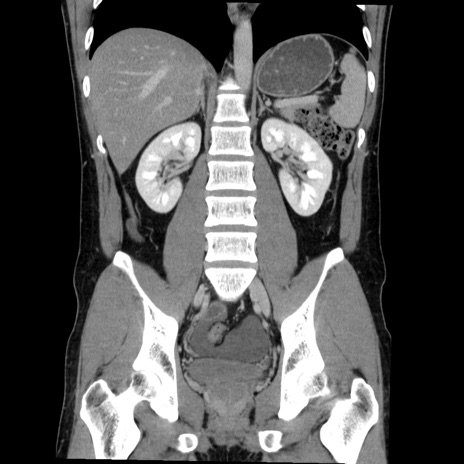

症例36(冠状断像)

【症例】20歳代 男性

【主訴】心窩部痛

【現病歴】今朝より上腹部痛あり。一旦軽快していたが再度出現したため救急要請。昨日夕に白身の魚を含む刺身を食べた。

【身体所見】BP 136/89mmHg、HR 74/min、BT 37.0℃、腹部:膨満、軟、心窩部に圧痛あり。反跳痛なし、筋性防御なし、腸雑音やや亢進あり。

【データ】WBC 17700、CRP 0.48